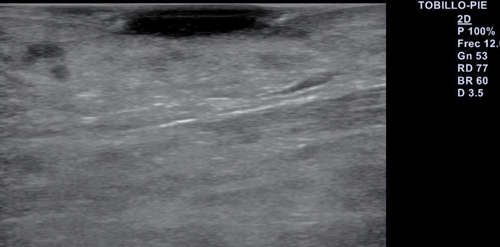

Se realiza exploración ecográfica vascular empleando para ello un equipo Alpinion E-cube 7 con una sonda lineal de 3-12 mHz, con una frecuencia de 12 mHz en la que destaca insuficiencia venosa y onda trifásica en arterias pedia y tibial posterior. Se realiza ecografía transulcerosa (Figura 2) mostrando área anecoica con punteado hiperecoico en su interior y con leve refuerzo acústico posterior, que afecta a la totalidad de la epidermis y penetra en dermis. Lesión bien delimitada, con ausencia de doppler en el interior de esta (Figura 3). Presenta una extensión ecográfica de 14 x 3.4 mm.

Figura 2. Ecografía transulcerosa en la que se observa la imagen anecoica con el punteado hiperecóico.